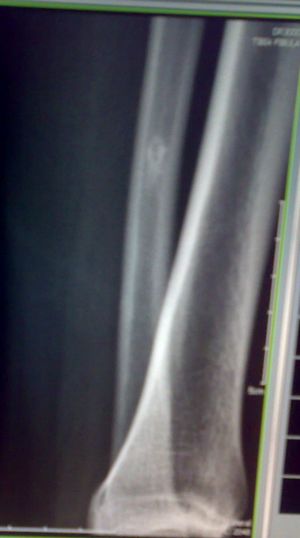

标题: X7846:M 20岁 外伤来诊。良性骨肿瘤吗? [打印本页]

标题: X7846:M 20岁 外伤来诊。良性骨肿瘤吗?

腓骨中下段骨皮质下不规则高密度影,侧位呈水滴形。外伤,估计平时没有症状,结合病人年龄,支持纤维性骨皮质缺损